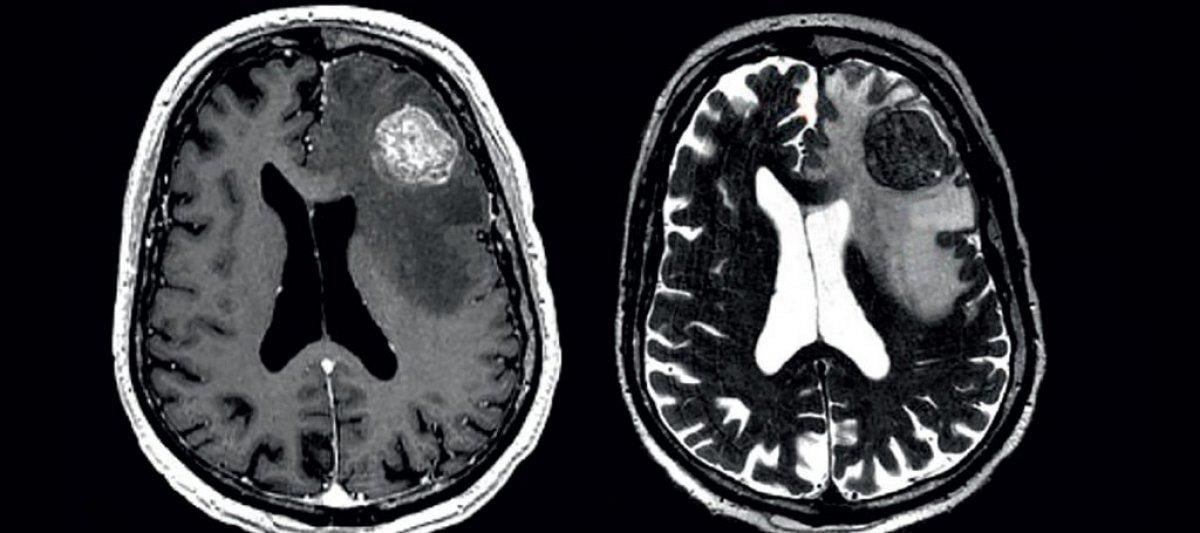

Bütün beyin tümörlerinin yüzde 30'unu oluşturduğu bilinen gliomlar, çoğunlukla kötü huyludur. Hastalığın ortaya çıkış nedeni ise net olarak bilinmemektedir.

Astrositom: Adını beynin içinde bulunan yıldız şeklindeki hücrelerden yani astrositomlardan alan tip, kötü huylu gliom türleri arasında en çok rastlanandır.